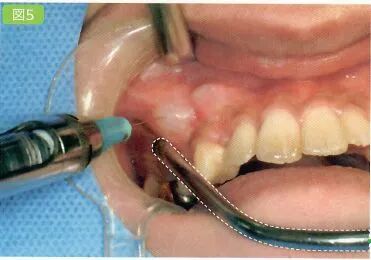

3 切开

利用手术刀·电刀等器械将手术区域的牙龈切开

医生利用手术刀进行切开。首先避免吸唾器在手术刀的切开路线上阻碍医生的操作。切开线设计分为三角形,四边形和沿牙龈缘等各种不同的形状。口腔卫生士一定要事先与医生确认切开设计的形状。

切开线设计(有残根的情况)

务必保证切开线区域的视的野晰度(切开前要吸引唾液,切开过程中要吸引血液)

切开前,一定要将切开线区域的唾液吸引干净。如果切开区域有唾液残留的话,会造成医生无法找到切开线路。切开时,从切开线区域会有血液溢出。将吸唾器放置到出血点,正确找到出血点才能更加有效的将溢出的血液吸引干净。